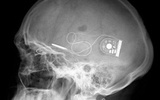

新型芯片可植入脑内 帮助盲人重见光明

德国科学家近日发明出一种可以微型芯片,可以植入病人脑内,放置于眼球后方,通过电力刺激病人的视觉神经,从而帮助一些盲人成功恢复视力。